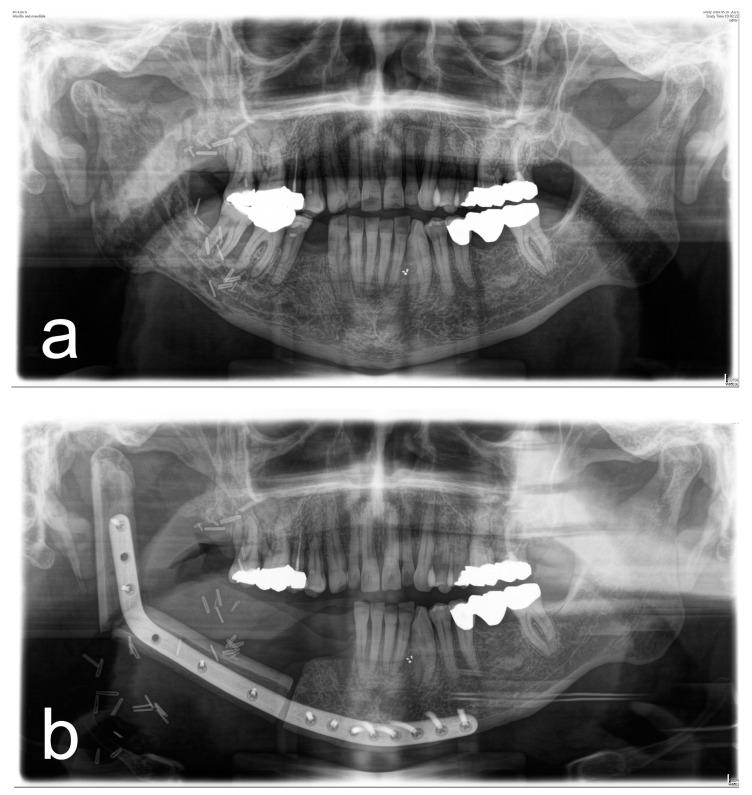

Surgical therapy of osteoradionecrosis of the jaw (ORN) is challenging and requires treatment of the affected hard and soft tissue. To understand how tissue injury after irradiation influences surgical outcomes, the objective of this study was to find out whether (a) bone-related, (b) soft tissue-related, and (c) treatment-related parameters influence the surgical success of patients with ORN. A total of 175 patients (324 lesions) were included in this retrospective, single-center study. All patients were diagnosed with ORN and underwent surgical therapy. The primary outcome was complete soft tissue recovery (mucosa/skin) and the absence of symptoms 3 months after surgery. At the time of follow-up, 58% of patients (189 of 324 lesions) had intact intraoral or extraoral soft tissue. The extent of bone destruction had no effect on treatment success, whereas soft tissue injury due to fibrosis (OR: 0.344; CI 0.142-0.834; = 0.01818) and xerostomia (OR: 0.163; CI 0.064-0.419; = 0.00016) increased the probability of treatment failure. Soft tissue reconstruction with a microvascular graft improved therapeutic success compared to local wound closure (OR: 2.998; CI 1.371-6.555; = 0.006). Thus, for the treatment of ORN, it is extremely important to pay attention not only to the extent of bone destruction but especially to soft tissue defects. Because the extent of soft tissue injury is a predictor for therapeutic success, it should influence the choice of surgical treatment.

颌骨放射性骨坏死(ORN)的手术治疗具有挑战性,需要对受影响的硬组织和软组织进行治疗。为了解放疗后组织损伤如何影响手术效果,本研究的目的是确定(a)与骨相关的、(b)与软组织相关的以及(c)与治疗相关的参数是否会影响ORN患者的手术成功率。本项回顾性单中心研究共纳入了175例患者(324个病灶)。所有患者均被诊断为ORN并接受了手术治疗。主要结局是术后3个月软组织完全恢复(黏膜/皮肤)且无症状。在随访时,58%的患者(324个病灶中的189个)口腔内或口腔外软组织完整。骨破坏程度对治疗成功没有影响,而纤维化导致的软组织损伤(OR:0.344;CI 0.142 - 0.834;P = 0.01818)和口干(OR:0.163;CI 0.064 - 0.419;P = 0.00016)增加了治疗失败的可能性。与局部伤口缝合相比,采用微血管移植进行软组织重建可提高治疗成功率(OR:2.998;CI 1.371 - 6.555;P = 0.006)。因此,对于ORN的治疗,不仅要关注骨破坏程度,尤其要关注软组织缺损,这极为重要。由于软组织损伤程度是治疗成功的预测指标,它应影响手术治疗的选择。